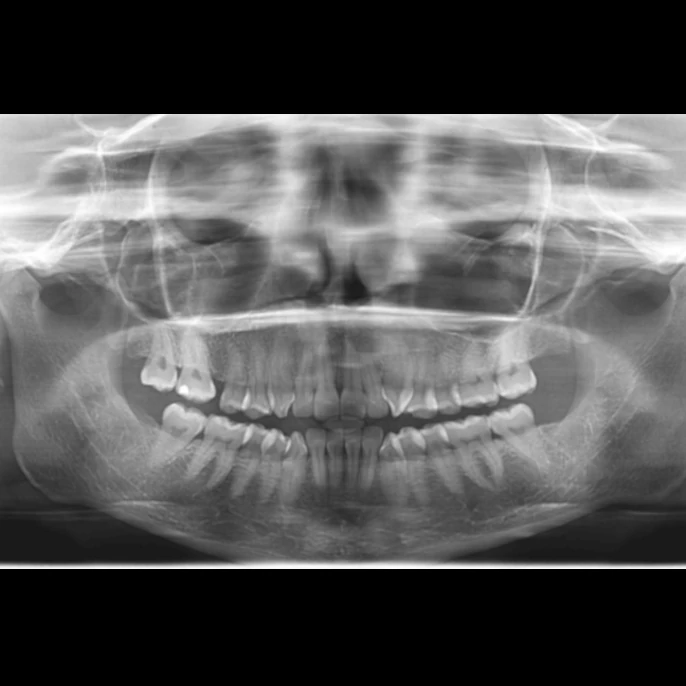

Estudios 2D

- Radiografía Panorámica.